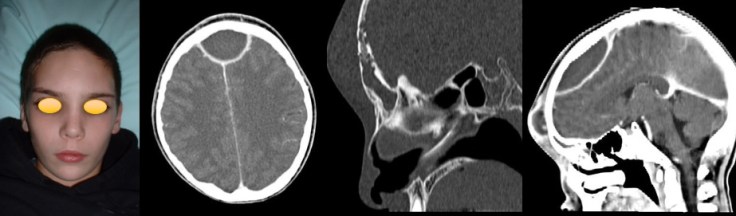

lorsqu’il existe une ostéite frontale importante associée à un empyème volumineux, le tableau clinique est assez caractéristique, avec un oedème fronto-orbitaire massif, chémosis et tableau infectieux sévère : c’est la pseudo-tumeur de Pott (Pott’s puffy tumor).

le diagnostic repose sur l’IRM mais le scanner est nécessaire pour juger de l’étendue de l’ostéite crânienne

il nécessite l’évacuation de la collection purulente et la résection de l’os ostéitique, et une antibiothérapie adaptée et prolongée.